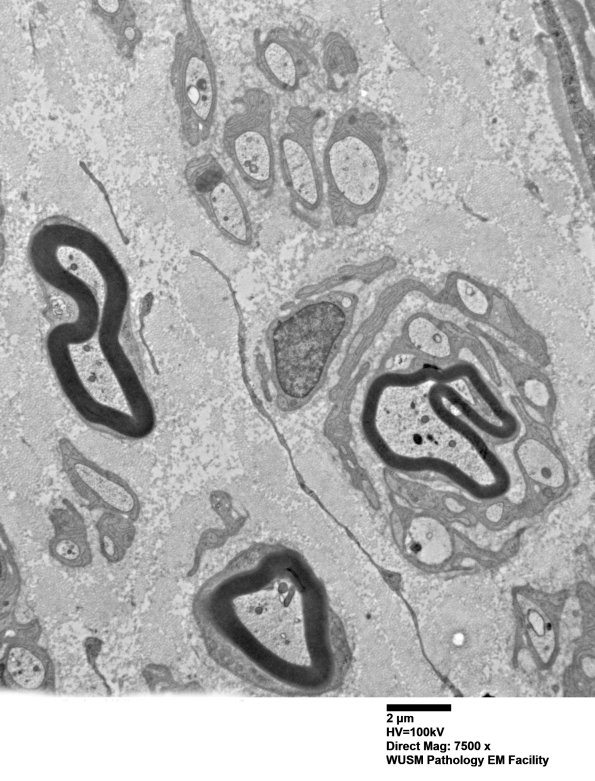

Washington University Experience | PERIPHERAL NEUROPATHY | 20 PSEUDO-ONION BULBS | 6C3 (Case 6) EM016 - Copy

6C3-5 A number of myelinated axons, not compellingly demyelinated, are surrounded by Schwann cell processes forming POB. There are numerous unmyelinated axons which are represented in many cases by “singletons” (single unmyelinated axons per Schwann cell unit). There are numerous bands of Büngner, some with lipidic debris and scattered lipofuscin. There are numerous axons with thinned myelin for axon caliber and regenerative clusters, evidence of axon degeneration with regeneration. Genuine onion bulbs are not present, nor are demyelinated axons, macrophage mediated demyelination or significant inflammation.